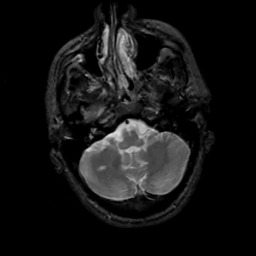

MR Study #5, March 10, 1991 -- Slice #11

[Home][Help][Clinical][Tour 1][Tour 2] Slice 11